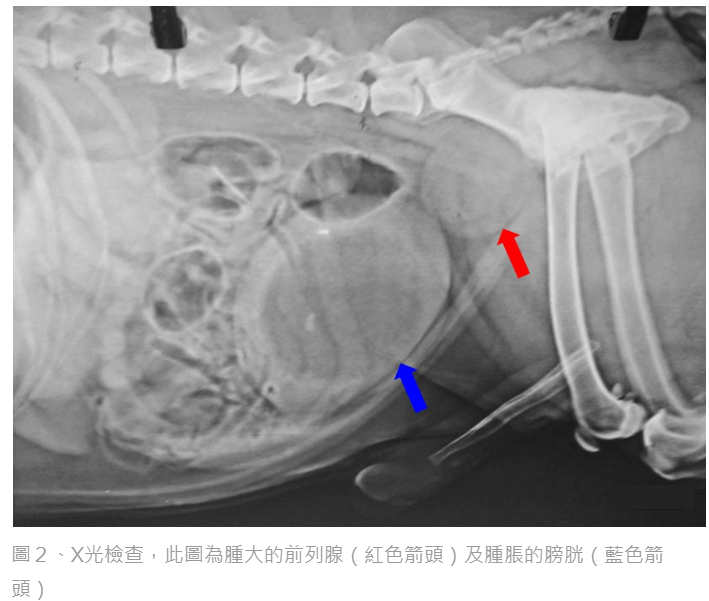

簡單方式是透過直腸觸診檢查是否腫大,但範圍有限。較準確的方式是拍攝X光或超音波影像,以檢查前列腺大小與構造是否異常。